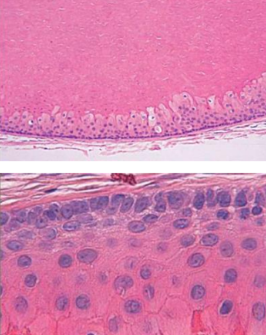

玻片特徵

- Developmental cyst

- epithelial lining 與結締組織交界處平整

- 非發炎型(noninflamed)

- 結締組織鬆散

- 糖胺聚醣基質(glycosaminoglycan ground substance)。

- 發炎型(inflamed)

- 網嵴(rete ridges)

- cholesterol clefts

- 齒源 → Rushton bodies

- true cyst

- 兩到四層的扁平非角化上皮

| 4-8 層、副角化(有核)、Basal cell 為 palisaded(柵狀) | |||||

basal cell reverse polarity  |

ghost cells (嗜酸無核)  |